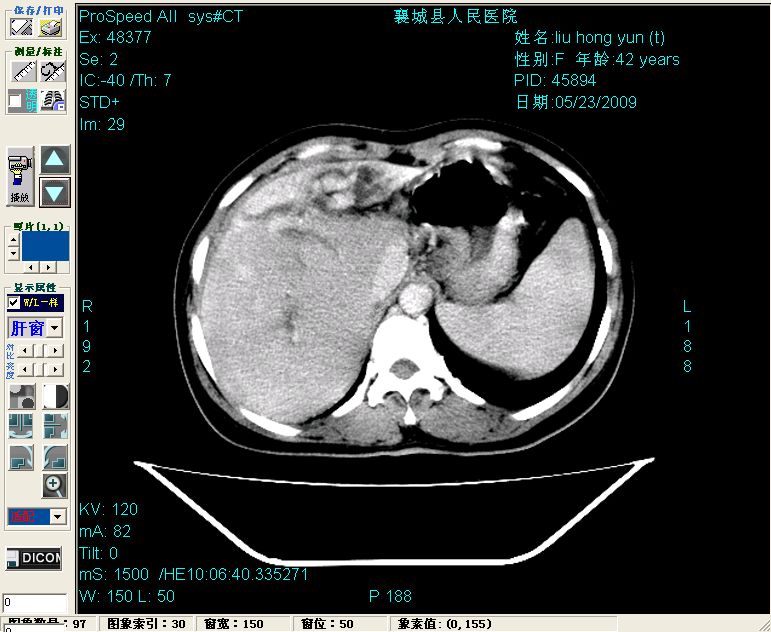

平扫:

平扫左肝外叶体积显著减小,左肝外叶见多房囊性低密度区,左肝实质及右肝前叶浅表实质呈低密度改变,左肝及右肝前叶胆管扩张,脾大

增强动脉期前述低密度区轻度早其强化,门脉期强化程度显著增高,延期扫描强化程度下降,但仍为相对高密度影

2左肝及右肝前叶表现考虑胆囊摘除术后所致的肝动门脉瘘形成,慢性纤维组织炎性增生.不完全除外左肝胆管细胞癌

3脾大,可能与动门脉瘘所致门脉高压有关